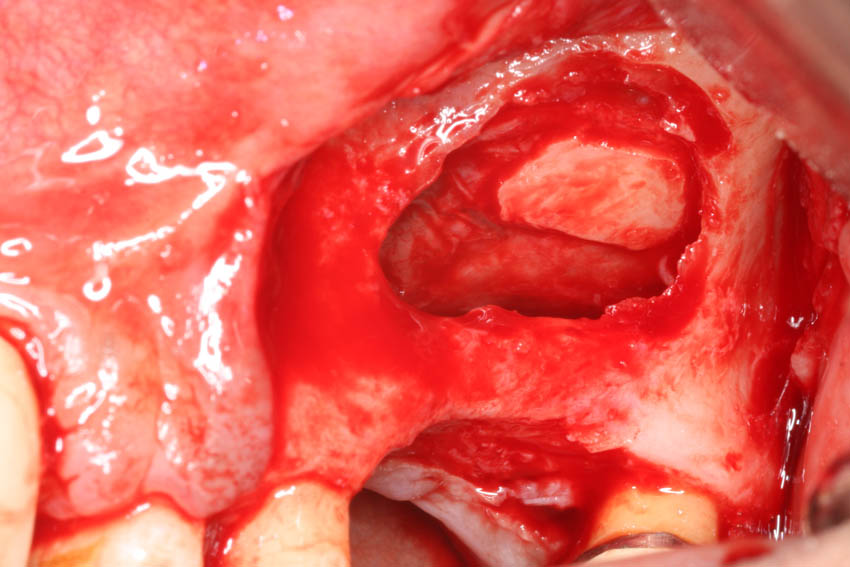

→ Ανύψωση του εδάφους του ιγμορείου με τη μέθοδο του οστικού παραθύρου.

→ Λήψη μοσχεύματος αυτογενούς οστικού μπλοκ από τον κλάδο.

→ Τεχνική διχασμού της φατνιακής ακρολοφίας για τη διεύρυνση του εύρους της.

→ Λήψη οστικών κόκκων αυτογενούς οστικού μοσχεύματος.

→ Ατραυματική εξαγωγή δοντιών με τα πιεζοηλεκτρικά άκρα σχήματος συνδεσμοτόμου.